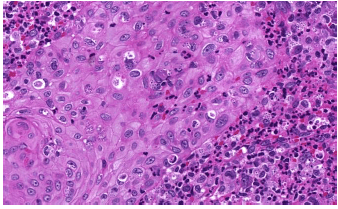

Homem, 52 anos, com lesão de pele que evoluiu com ulceração. Observe a imagem abaixo. Assinale a alternativa que apresenta o diagnóstico que a figura ilustra.